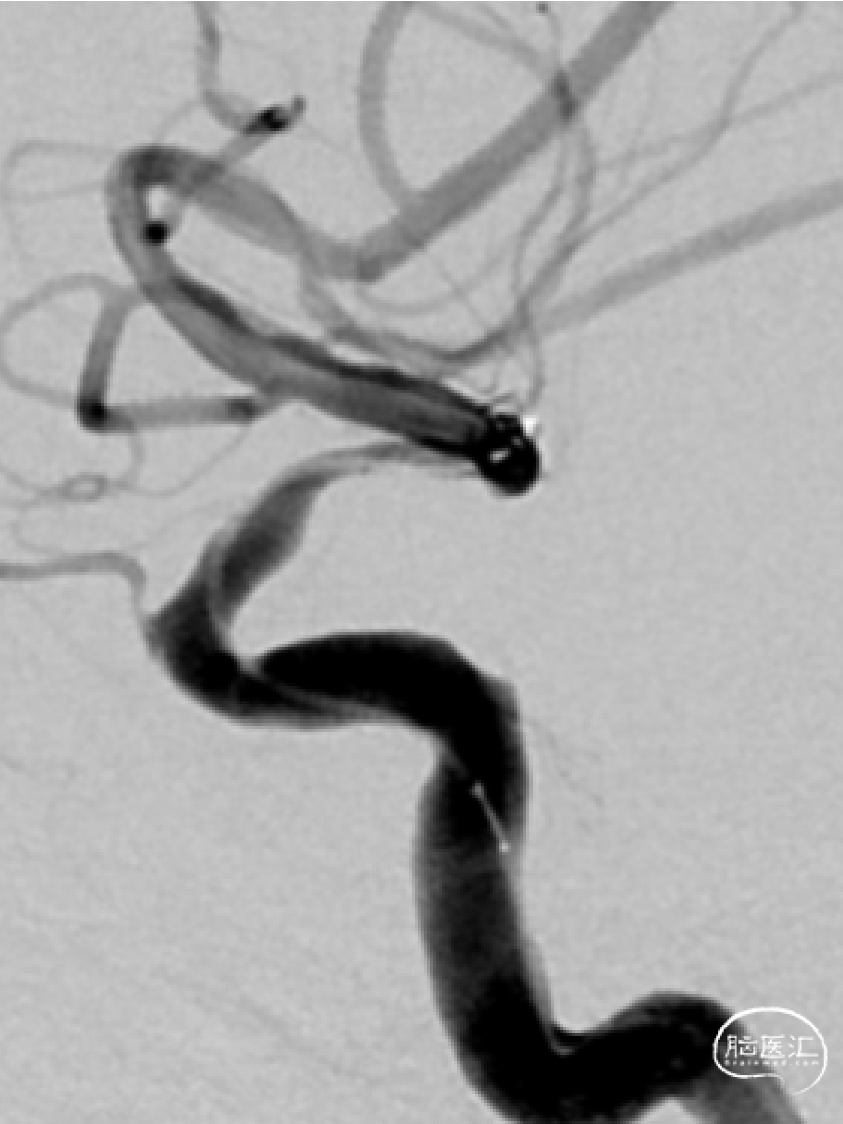

➢DSA(2023.11.10)

右侧M1段动脉瘤

植入Atlas支架,动脉瘤不显示,狭窄改善。

术后正侧位。